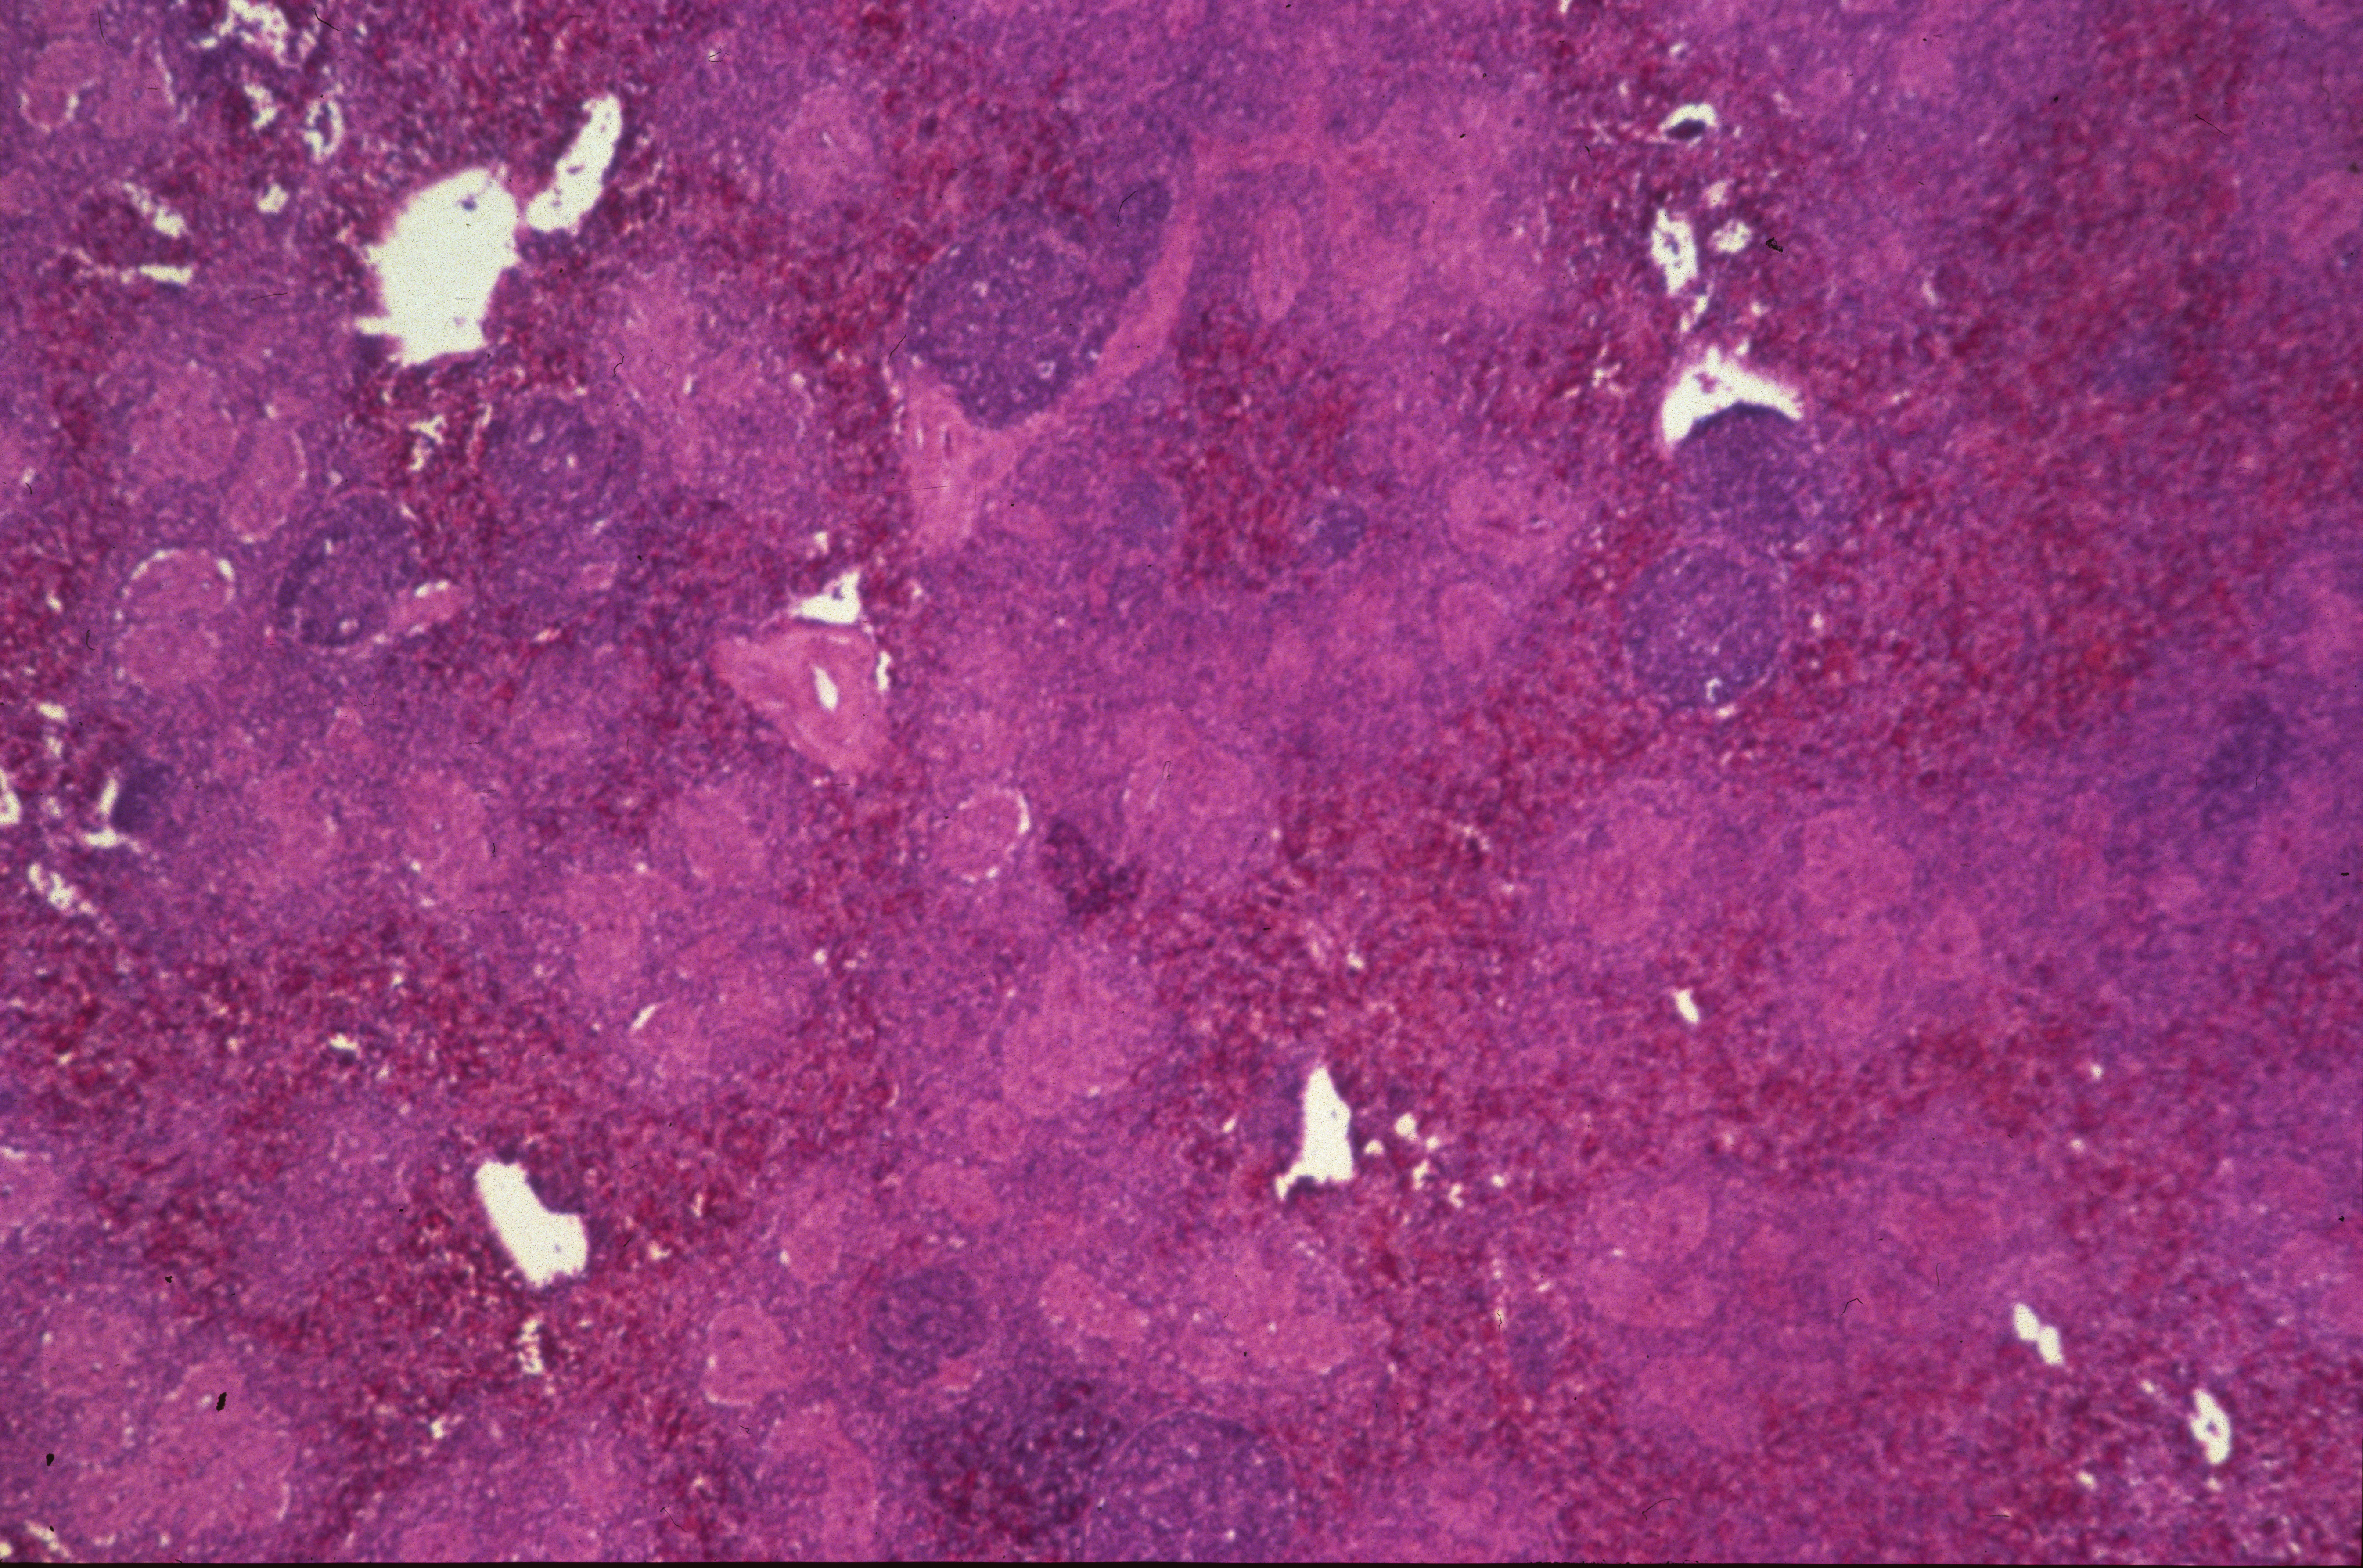

Marble spleen disease of ring-necked pheasants (slide study set no. 17) Item Info

Marble spleen disease of ring-necked pheasants (slide study set no. 17)

Slide study set #17, marble spleen disease of ring-necked pheasants, 2 sets (includes 40 color slides), undated